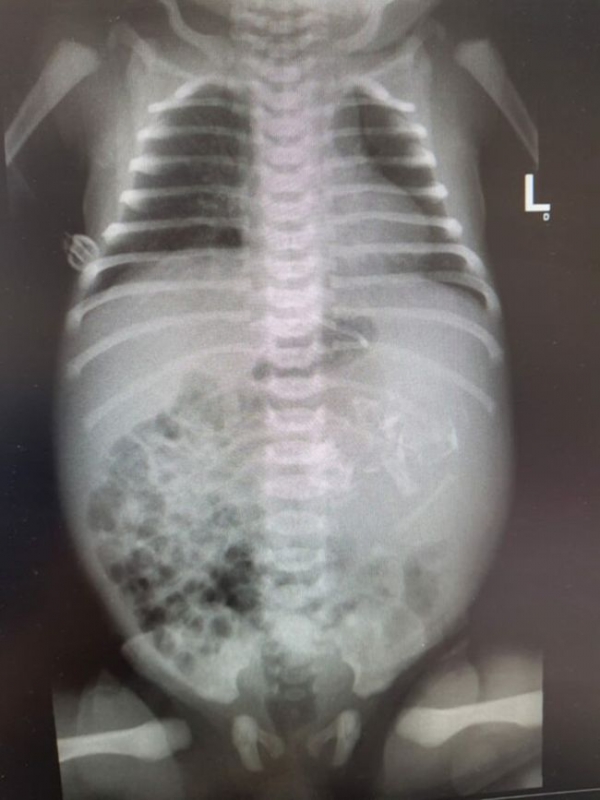

医疗小组随后迅速进行了进一步的超声波和x光检查。阿苏塔大学的新生儿学主任奥马尔·加尔布斯(Omer Globus)说,他们对于这是个胚胎还是很惊讶的。医疗中心的一组医生进行了手术,最终从女孩的胃中取出了两个类似的囊。他们认为那里不止一个,仍在核实。